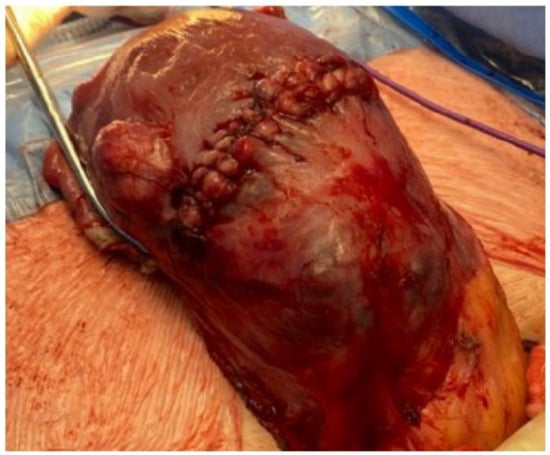

2. Case 1: History, Investigations, Treatment, and Outcomes